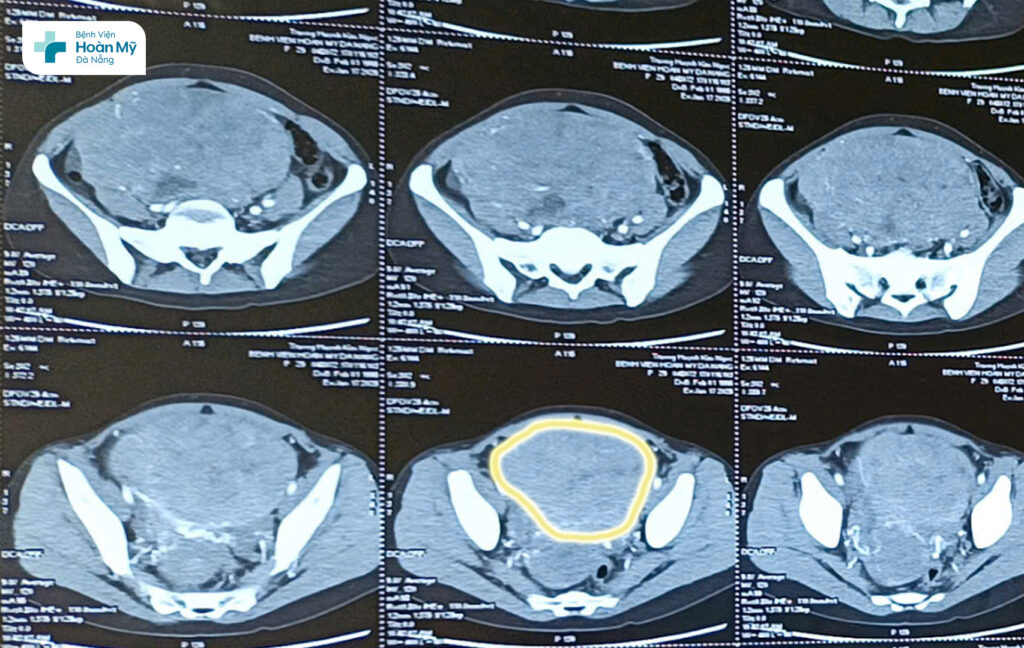

Tại Bệnh viện Hoàn Mỹ Đà Nẵng, qua thăm khám lâm sàng, siêu âm, chụp cắt lớp vi tính có cản quang, kết quả xác định phía đáy mặt ngoài tử cung của chị K có khối u kích thước lớn (19x16cm) choán đầy trong vùng tiểu khung và có các ổ dịch đã hoại tử. Khối u cũng chèn đẩy các cấu trúc lân cận, chèn niệu quản phải gây thận ứ nước độ 1.